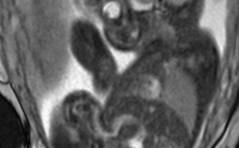

Sonoquiz 03/23

Was fällt kaudal des Nabels auf? PDF Dokument

Auflösung Sonoquiz 03+04/2023

Auflösung Sonoquiz aus diesem Heft PDF Dokument